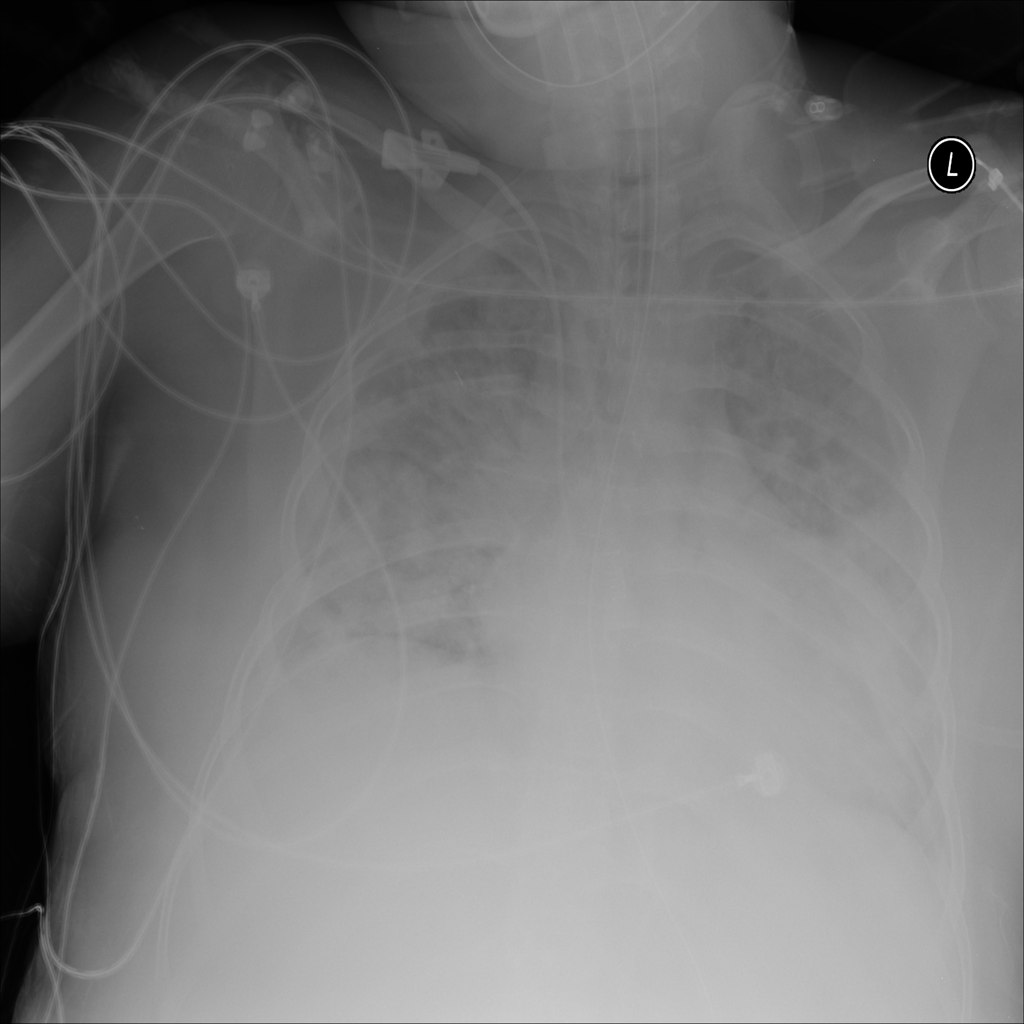

PAT-3384 · IMG-053Cardiomegaly

PAT-3384 · IMG-053

AP